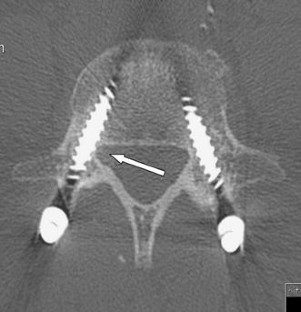

Fig. 1

Fig. 2

Fig. 3

Fig. 4

Fig. 5

Fig. 6

Fig. 7